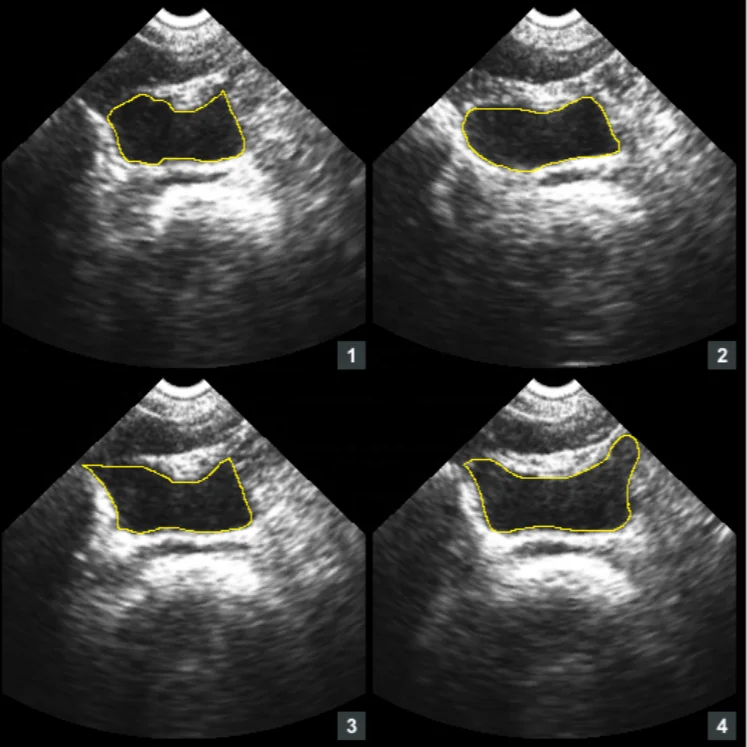

Это техническое нововведение для PBSV5.1 для обеспечения высокой точности так же, как выполнить сканирование проще, легкая и профессиональные режима сканирования.

Режим Expert: позволяет пользователям видеть изображения в реальном времени

Простой режим: отображение эскиза мочевого пузыря

• Ручная коррекция границы мочевого пузыря

Ручной контур отсканированных серых изображений для коррекции громкости, что позволяет избежать повторного сканирования